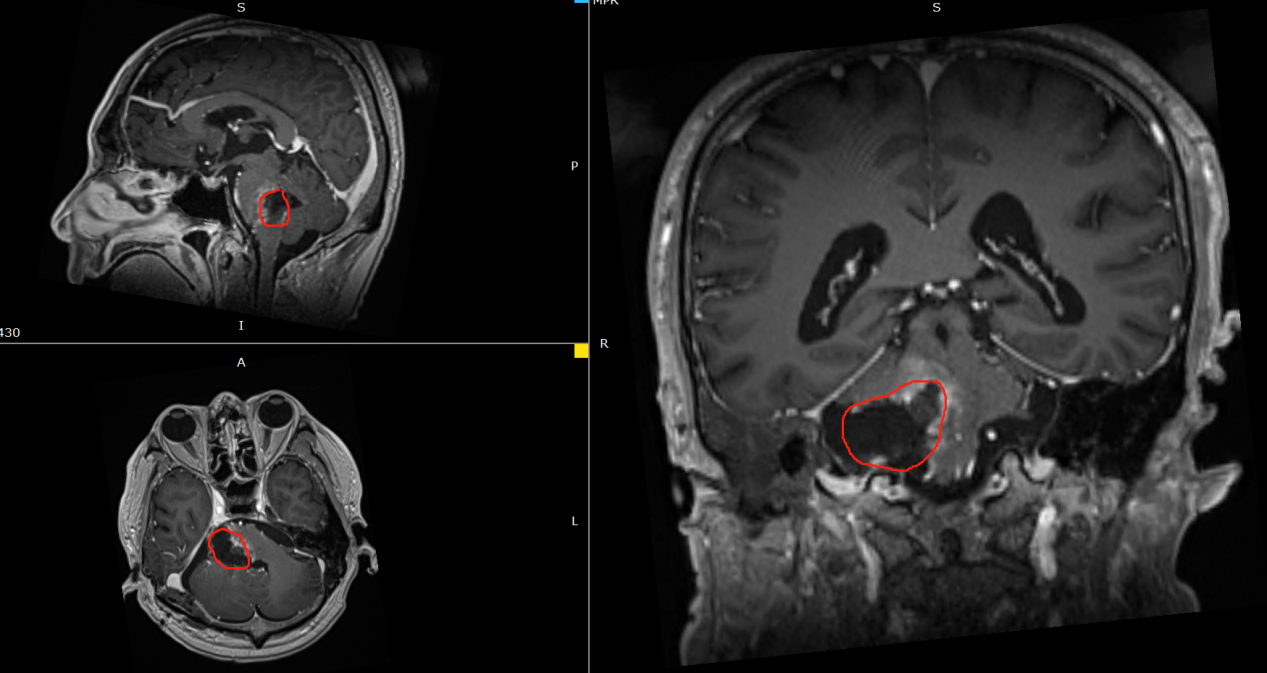

术前影像:右侧脑桥占位,与周围结构分界不清,脑干受压变薄,向左前移位。

术后影像:肿瘤占位被大部分切除,切除率95%以上。残余部分与脑干关系密切。